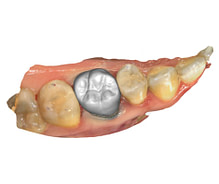

Improved Aesthetics

With advanced software, dentists can create restorations that closely match the color, shape, and size of a patient’s natural teeth. This results in a more natural and aesthetically pleasing appearance.

Crowns and Bridges

Inlays and Onlays